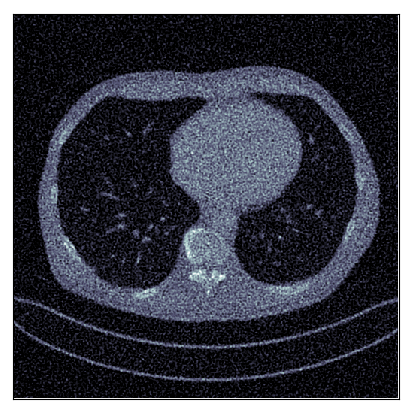

We consider the variational reconstruction framework for inverse problems and propose to learn a data-adaptive input-convex neural network (ICNN) as the regularization functional. The ICNN-based convex regularizer is trained adversarially to discern ground-truth images from unregularized reconstructions. Convexity of the regularizer is desirable since (i) one can establish analytical convergence guarantees for the corresponding variational reconstruction problem and (ii) devise efficient and provable algorithms for reconstruction. In particular, we show that the optimal solution to the variational problem converges to the ground-truth if the penalty parameter decays sub-linearly with respect to the norm of the noise. Further, we prove the existence of a sub-gradient-based algorithm that leads to a monotonically decreasing error in the parameter space with iterations. To demonstrate the performance of our approach for solving inverse problems, we consider the tasks of deblurring natural images and reconstructing images in computed tomography (CT), and show that the proposed convex regularizer is at least competitive with and sometimes superior to state-of-the-art data-driven techniques for inverse problems.